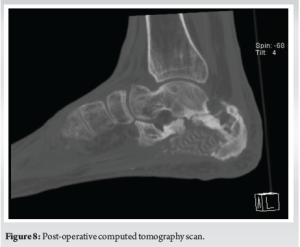

There was good restoration of calcaneal width, height, and alignment as well as subtalar and calcaneocuboid joint congruency. The critical-sized bone defect was adequately addressed with the use of the synthetic scaffold in conjunction with the Masquelet “induced membrane” technique incorporating autogenous iliac crest bone graft and BMAC. At 3 years post-operation, the patient is ambulant without walking aids, reports minimal pain, and remains infection-free. The surgical wounds are well healed, and the flap is healthy (Fig. 6). Repeat radiographs and CT scans show callus formation, bony fusion, and graft incorporation (Fig. 7 and 8). While there is some degree of interval collapse of the calcaneal height as well as subtalar and calcaneocuboid arthritis, the use of the synthetic scaffold provided a significant restoration of height as compared to the index injury radiographs.